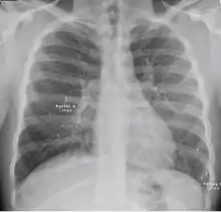

Radiology (X-rays) is used in the diagnosis of tuberculosis. Abnormalities on chest radiographs may be suggestive of, but are never diagnostic of TB, but can be used to rule out pulmonary TB.

A posterior-anterior (PA) chest X-ray is the standard view used; other views (lateral or lordotic) or CT scans may be necessary.

In active pulmonary TB, infiltrates or consolidations and/or cavities are often seen in the upper lungs with or without mediastinal or hilar lymphadenopathy.[1] However, lesions may appear anywhere in the lungs. In HIV and other immunosuppressed persons, any abnormality may indicate TB or the chest X-ray may even appear entirely normal.[1]